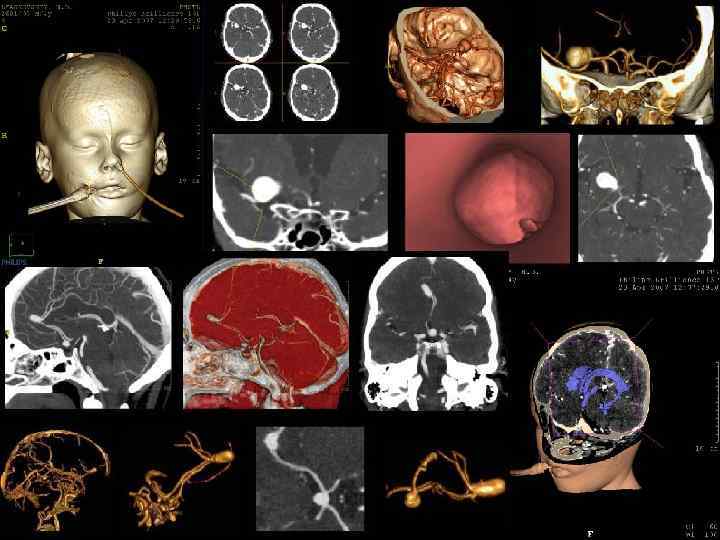

МРТ - ангиография